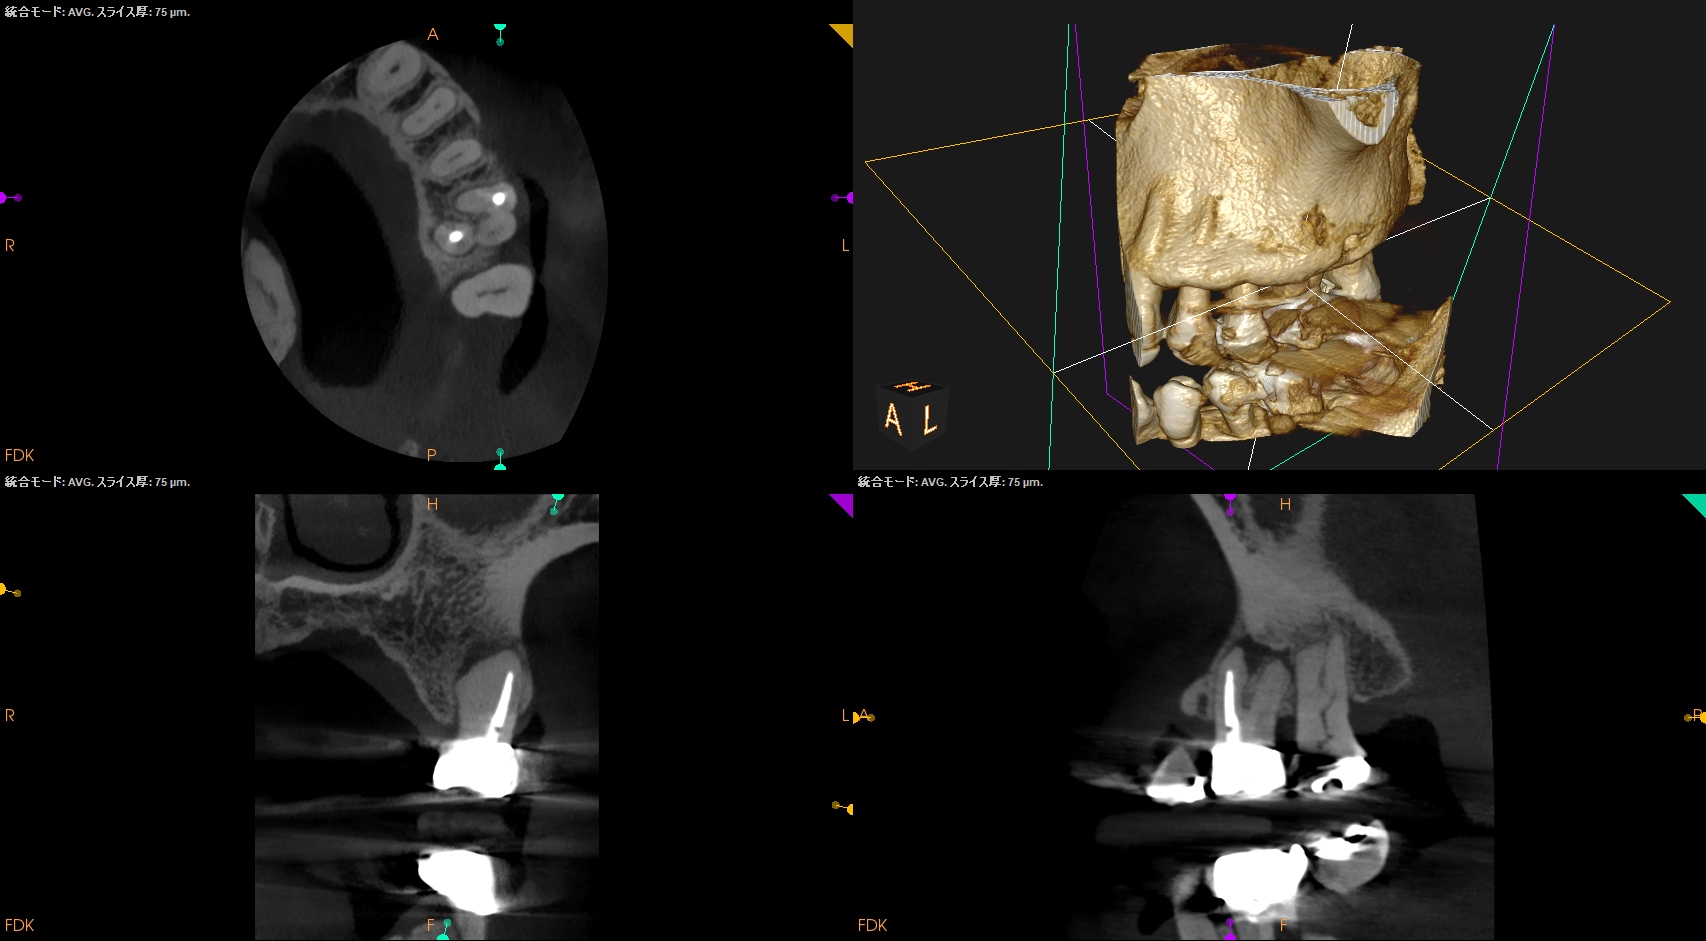

ということで治療時に以下のように修正した。

術後にPA, CBCTを撮影した。

問題はないだろう。

次回はMB,DBのApicoectomyである。